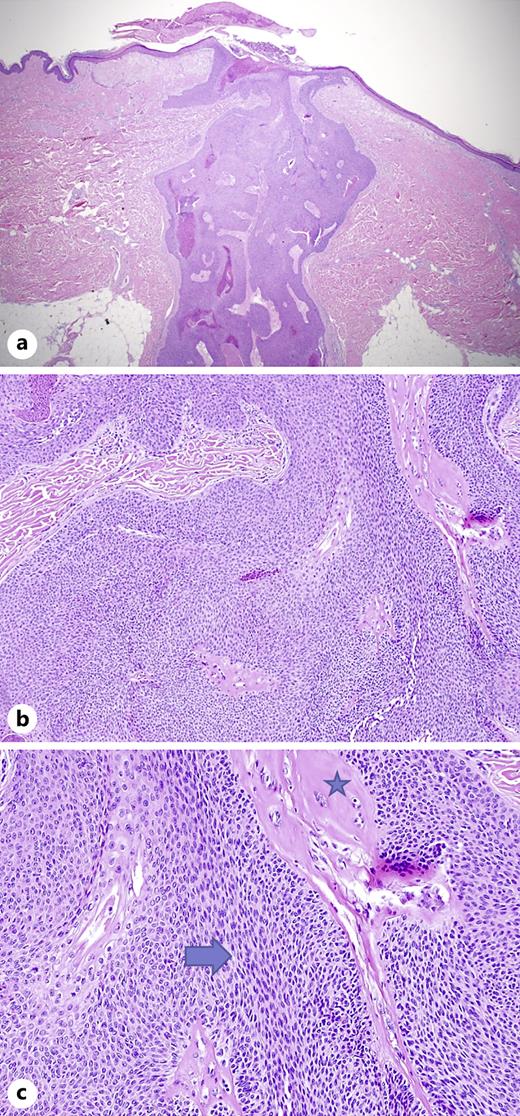

Keratoacanthomas and Squamous Cell Carcinomas on Tattoos A Review of